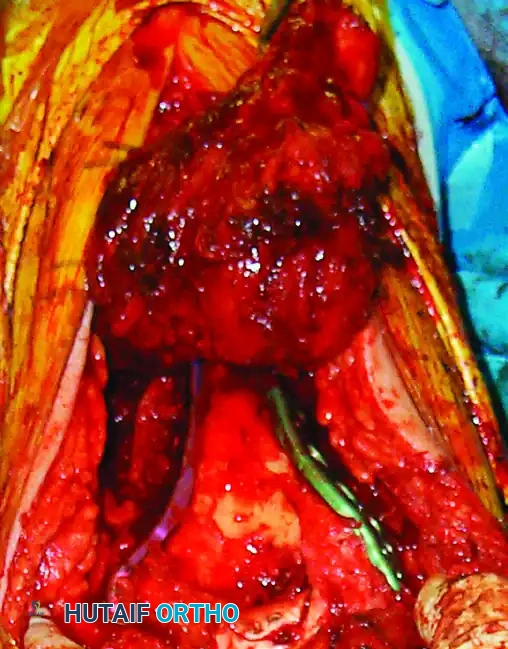

5. Fracture Reduction and Articular Reconstruction

With the distal humerus fully exposed, thoroughly débride the fracture edges to clean the surfaces of hematoma and interposed soft tissue.

The fundamental principle of complex distal humerus ORIF is to convert a Type C (intra-articular bicolumnar) fracture into a Type A (extra-articular) fracture by first reconstructing the articular block.

• Complex Articular Comminution: Reconstruct the articular surface "around the clock." Provisionally fix the reconstructed fragments. If either the medial or lateral condyle has a good "key" to reduction with the humeral shaft, reduce that condyle to the shaft first.

• A countersunk mini-fragment (2.0-mm or 2.4-mm) lag screw can be used for provisional or definitive fixation of the articular block because its low profile will not interfere with subsequent plate positioning.

• Use headless compression screws, mini-fragment screws, or absorbable screws for the fixation of small osteochondral fragments and articular comminution.